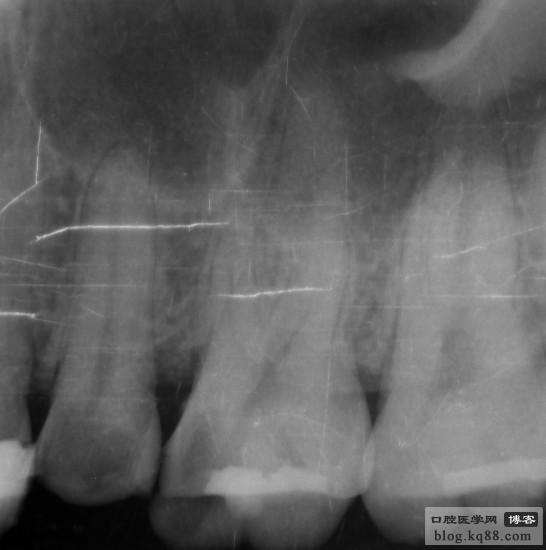

右上5、6